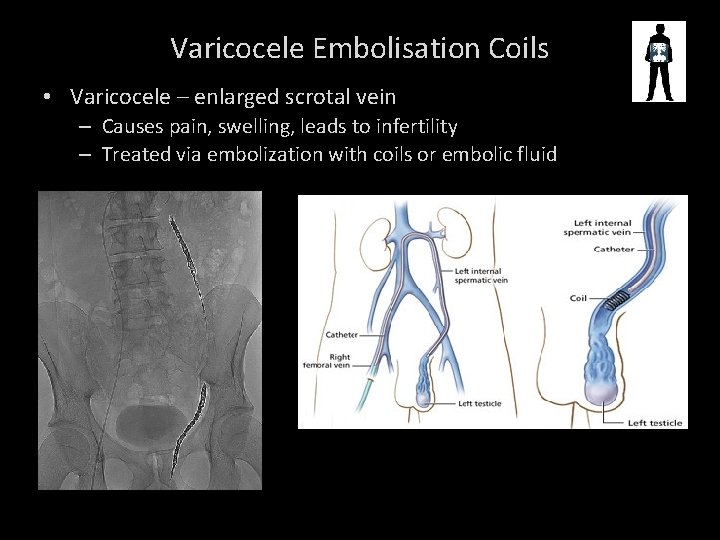

Varicocele Embolisation Coils • Varicocele – enlarged scrotal vein – Causes pain, swelling, leads to infertility – Treated via embolization with coils or embolic fluid